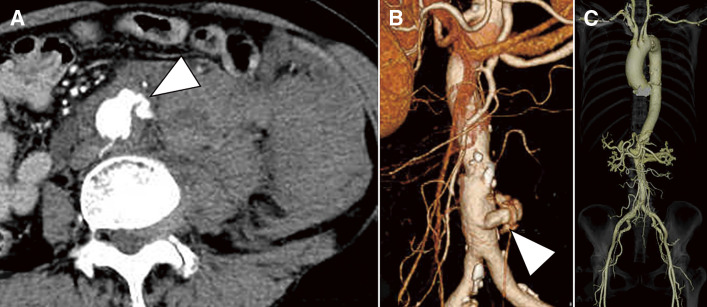

我们报告一例腹主动脉破裂无动脉瘤合并巨细胞动脉炎。一名67岁女性,以腰痛为主诉。增强计算机断层扫描显示腹膜后大量血肿伴腹主动脉造影剂泄漏,提示腹主动脉破裂。急诊手术中发现腹主动脉前壁破裂,未见动脉瘤样改变或腹主动脉扩张。切除的主动脉壁组织病理学检查显示CD68阳性巨细胞浸润,诊断巨细胞性动脉炎。

We report a case of an abdominal aortic rupture without aneurysm associated with giant cell arteritis. A 67-year-old woman presented with lower back pain. Contrast-enhanced computed tomography revealed a massive retroperitoneal hematoma with contrast leakage from the abdominal aorta, suggestive of abdominal aortic rupture. During emergency surgery, a rupture site was identified on the anterior wall of the abdominal aorta, while no aneurysmal changes or dilatation of the abdominal aorta were observed. Histopathological examination of the resected aortic wall revealed infiltration of giant cells positive for CD68, leading to the diagnosis of giant cell arteritis.